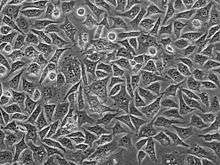

PC3

PC3 (PC-3) human prostate cancer cell lines are one of the cell lines used in prostate cancer research. These cells are useful in investigating the biochemical changes in advanced prostatic cancer cells and in assessing their response to chemotherapeutic agents. Moreover, they can be used to create subcutaneous tumors in mice in order to investigate a model of the tumor environment in the context of the organism.

Furthermore, karyotypic analysis has shown that PC3 are near-triploid, presenting 62 chromosomes. Q-band analysis showed no Y chromosome. From a morphological point of view, electron microscopy revealed that PC3 show characteristics of poorly-differentiated adenocarcinoma. They have features common to neoplastic cells of epithelial origins, such as numerous microvilli, junctional complexes, abnormal nuclei and nucleoli, abnormal mitochondria, annulate lamellae, and lipoidal bodies.